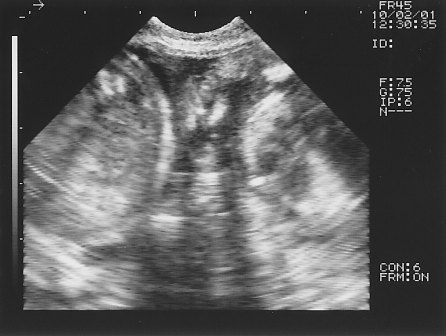

予定日まで1週間ほどになり、エコー検査の時期到来☆

胎児の心臓や肝臓、肋骨に至るまでが写り~の

今回のエコーで、3頭のパピーが確認できました。